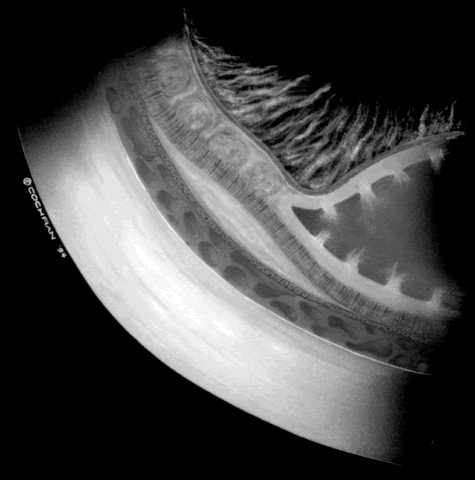

The techniques of vitreous surgery in children require an understanding of the anatomy of the pars plicata. A premature child does not have a well-defined pars plana, and therefore pars plicata entry is the only entry possible to avoid the lens upon entering the vitreous cavity. A term infant who is 8 months post term has a 2 mm pars plana.12 Infants who are premature at the time of vitreous surgery require entry immediately posterior to the iris root to avoid damage to the neurosensory retina and crystalline lens. After vitreous surgery, particularly one that is lens-sparing, the final visual result depends on the child's central nervous system, refractive status, and competition with the fellow eye. With lens-sparing vitrectomy techniques, however, visual acuities can be made as good as 20/60, even in ROP cases.26,27 The child who has lensectomy/vitrectomy as well as membrane peeling with appropriate refractive correction can have a visual acuity as good as 20/200 to 20/400.28 The child's initial aphakic status can greatly affect his or her final visual outcome. This is why we believe strongly that prompt screening in order to time surgical intervention appropriately as well as reacting quickly to the child's surgical need are important means of optimizing final visual outcome. A child's refractive status is always difficult to deal with, especially if the child is aphakic or the red reflex is compromised. In children, we should not forget the need to assess near vision and the use of low vision aids. A child's retinal detachments progress at variable rates; thus the rate of detachment must be assessed on an individual basis. In children with RUSH disease, the eye has a very immature retina with much of the vascularized/avascular retinal juncture in zone 1. These eyes tend to progress to retinal detachment very quickly, often within 1 to 2 weeks. We have described another uncommon entity called very posterior zone 1 retinopathy of prematurity.29 In this disease, the macula is disorganized and not clearly visible. The posterior pole presents a syncytium of vessels all in zone 1. All of these eyes that we followed have gone on to have tractional retinal detachment. If there is to be any hope of vision in these patients, management requires a very rapid and broad peripheral ablative treatment followed by early vitreous surgery intervention. The care of ROP patients requires a careful and rapidly performed screening examination, rapid intervention with peripheral ablation, scleral buckling, lens-sparing vitrectomy, or lensectomy/ vitrectomy and membrane peeling. Given a prompt intervention, we have come to believe that ROP can be managed with results comparable to those for patients with diabetes or proliferative vitreoretinopathy. To date, Droste and Trese30 are the only investigators to have reported on a consecutive series managed in that fashion, and this series showed improved visual results. Historically, visual results in ROP have been poor if retinal detachment intervention was delayed. With the advent of appropriate screening and rapid surgical intervention, however, improved visual results are possible. |